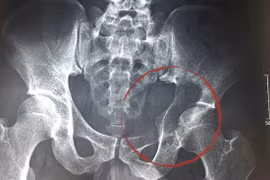

Một bệnh nhân nam 34 tuổi ở Nghệ An mang khối u “khủng“ nặng tới 45 kg đã được các bác sĩ Bệnh viện Việt Đức phẫu thuật cắt bỏ sau hàng chục năm gù lưng cõng khối u.